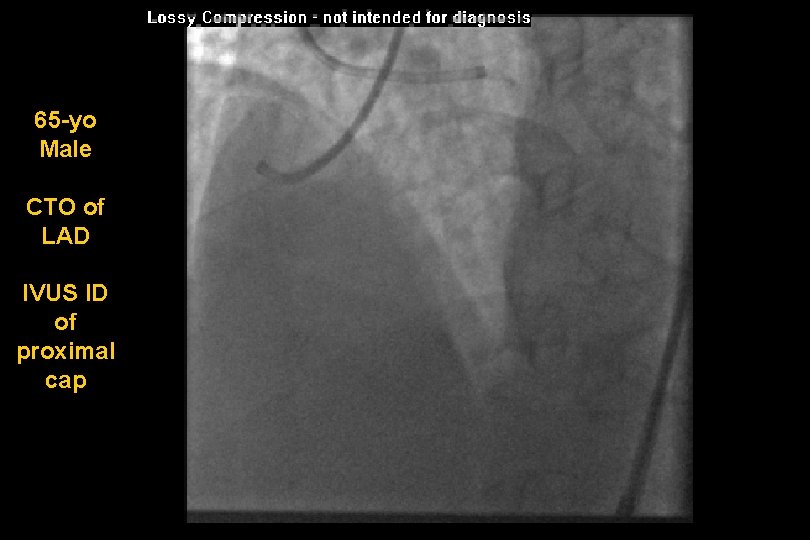

65 -yo Male CTO of LAD IVUS ID of proximal cap